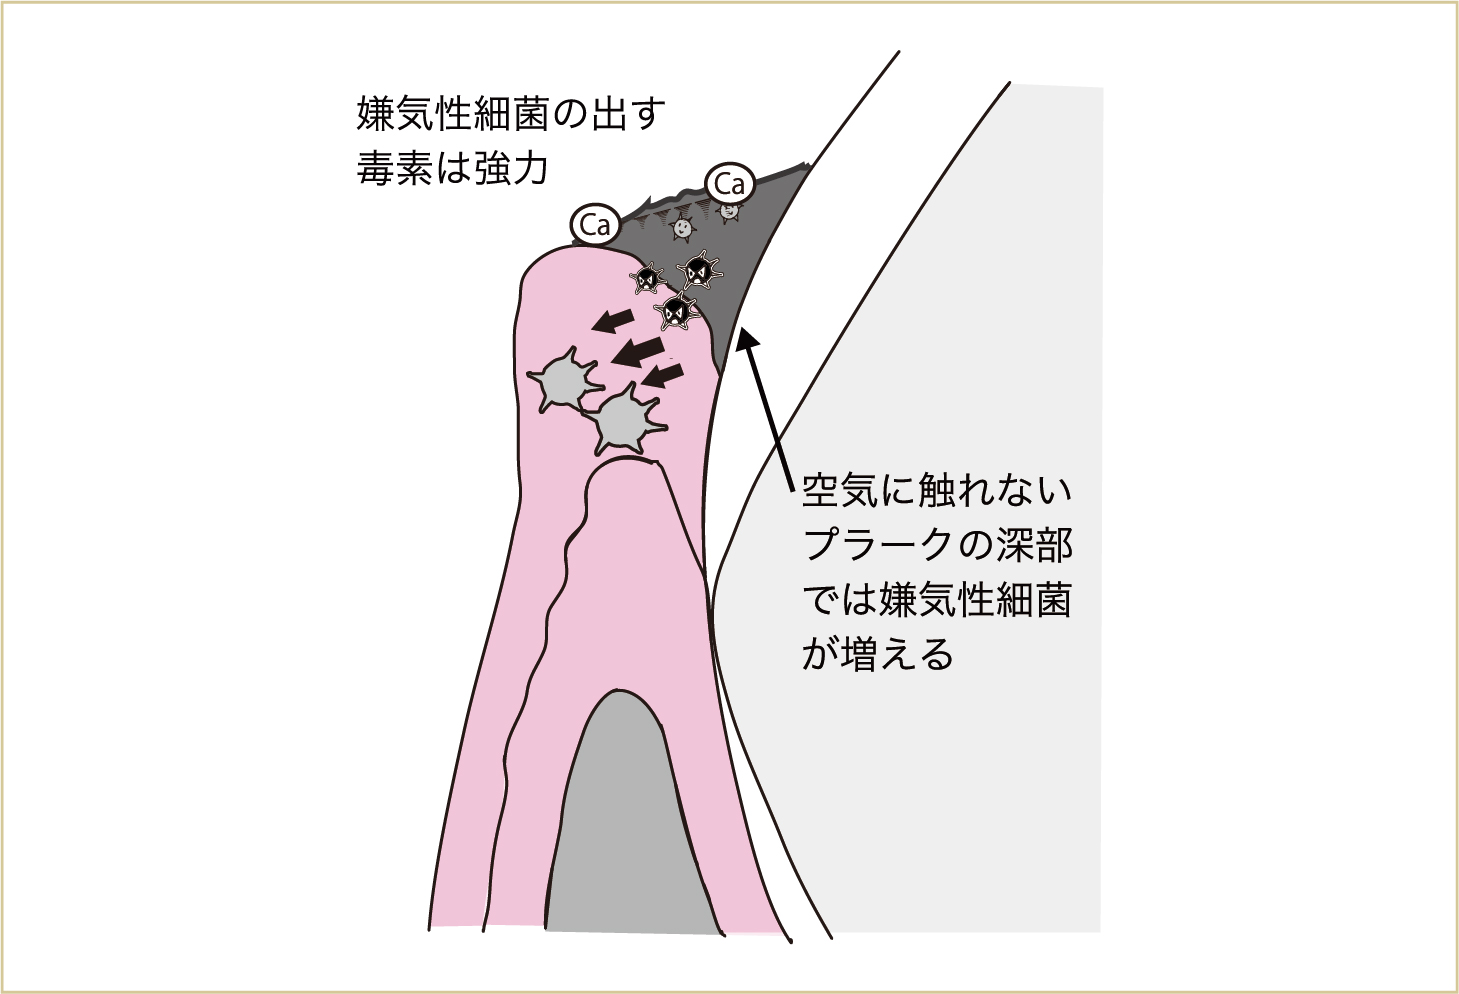

こうしたことが何度も繰り返されると、毎日の積み重ねで、最初についた汚れの部分には空気が触れなくなってきます(口腔内は普通、空気に触れている)。そうすると、空気がない所で元気になる細菌(嫌気性細菌という)が増えてきます。この嫌気性細菌が出す汗や老廃物(毒素)は、よりいっそう、歯肉などに対して毒性が強いのです。

みがき残しが何層にも降り積もると、初めについたみがき残しは空気が触れにくい環境になり、より毒性の強い菌(歯周病原菌、嫌気性細菌)が増えてくる。

表面が歯石でガードされているため、ブラッシングしても汚れはとれない。空気が触れにくい深部には、より毒性の強い菌が増える。そのため歯肉に多くの毒素が入り込み、歯と歯肉とのバリアが壊されていく。